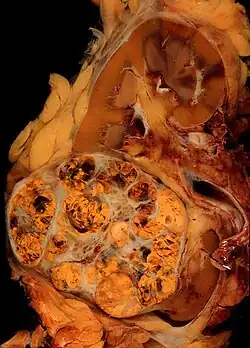

La apariencia macroscópica muestra un tumor multilobulado de color amarillento situado en la corteza renal, el cual con frecuencia contiene zonas de necrosis, hemorragia y fibrosis. Bajo el microscopio, se ven en el tumor células que forman cordones, papilas, túbulos o nidos y que tienden a ser células atípicas, poligonales y de gran tamaño. Debido a que estas células acumulan glucógeno y lípidos, su citoplasma tiene una apariencia clara con el núcleo celular central y una membrana plasmática evidente. Algunas células pueden ser de menor tamaño con un citoplasma rojizo o eosinofílico, muy similares a las células tubulares normales. El estroma se encuentra reducido y bien vascularizado. El tumor comprime el parénquima que le rodea, produciendo una pseudo-cápsula.[14] La producción y secreción de sustancias vasoactivas, como la renina, pueden causar hipertensión arterial y la liberación de eritropoyetina puede causar una producción aumentada de glóbulos rojos o eritrocitosis.